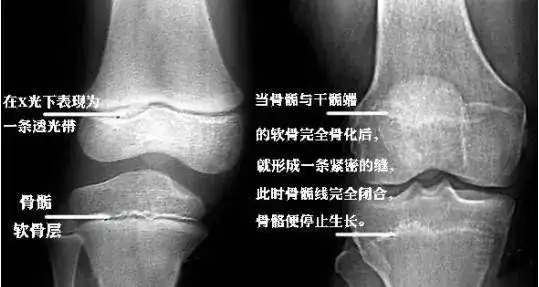

骨骺与骨干之间有一层软骨层,医学上称之为骺软骨 ( 骨骺线).

人体长高,依靠的是骨骺线,在骨骺与干骺端之间有一块软骨,软骨与骨垢

随着年龄的增长,这层骺软骨会逐渐消失,最终 完全骨化,骨骺线也

在未成年之前,骨两侧连接处为骺软骨,骺软骨在少年时期增生,骨化.